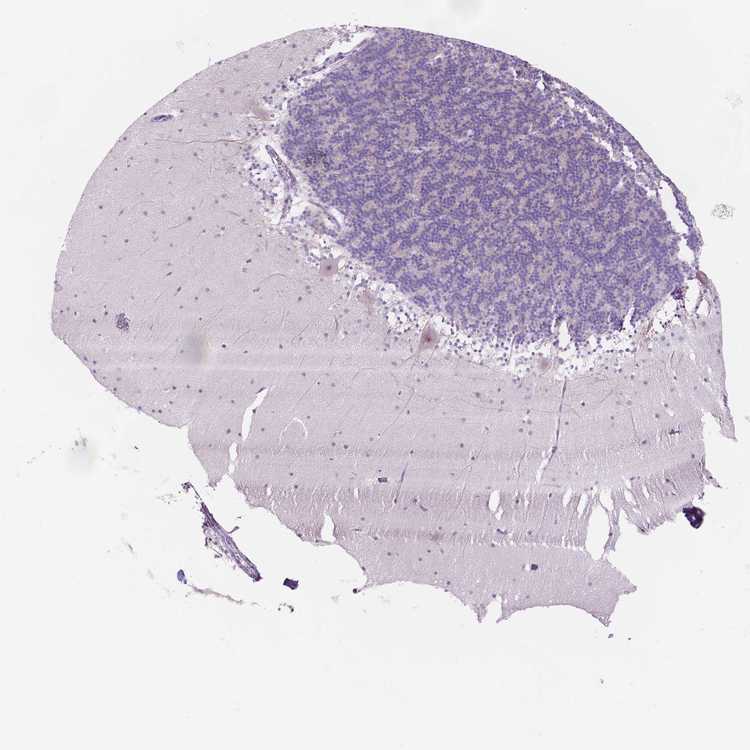

CEREBELLUM - Antibody stainingi

Antibody staining in the annotated cell types in the current human tissue is reported as not detected, low, medium, or high, based on conventional immunohistochemistry profiling in selected tissues. This score is based on the combination of the staining intensity and fraction of stained cells.

Each image is clickable and will lead to virtual microscopy that enables deeper exploration of all samples and also displays staining intensity scores, fraction scores and subcellular localization as well as patient and tissue information for each sample.

Antibody HPA069552

Purkinje cells Not detected

Cells in granular layer Not detected

Cells in molecular layer Not detected